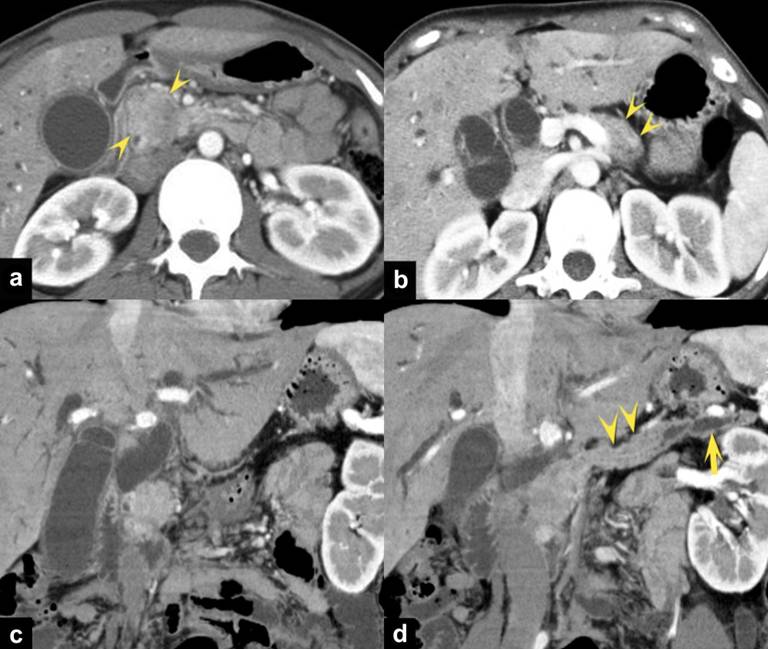

A 26-year-old woman was admitted to our hospital because of abdominal pain. Laboratory examination showed the elevated serum levels of bilirubin and hepatic enzymes. Her medical history was not remarkable. Laboratory findings showed abnormal liver function (AST: 118 IU/L, ALT: 91 IU/L) and obstructive jaundice (total bilirubin: 11.53 mg/dL). The carbohydreate antigen (CA) 19-9 (106 U/mL) was moderately elevated but the carcinoembryonic antigen (CEA) showed normal range. Triple-phase enhanced computed tomography (CT) demonstrated a well-enhanced mass on the arterial dominant phase in the head of the pancreas (Figure 1ac). The mass grew within the lumen of the MPD in the body of the pancreas, with dilatation of the upstream MPD (Figure 1bd). There was a difference of the contrast-enhancement pattern between the main tumor of the pancreatic head and the intraductal lesion of the pancreatic body: an early contrast-enhancement with its persistence till the delayed phase in the head lesion, and an early contrast-enhancement with its decrease during the delayed phase in the intraductal tumor of the body. Dilation of the bile ducts was seen probably due to the tumor compression, and direct tumor invasion to the duodenum was suspected. Lymph node enlargement at the portocaval space was identified, but there was no metastatic lesion in the major organs. On magnetic resonance (MR) imaging, the pancreatic head lesion was observed as non homogeneously low signal intensity (SI) on T2-weighted imaging (WI) (Figure 2a) and low SI on T1-WI (Figure 2b). The intraductal lesion of the pancreatic body showed high SI on T2-WI (Figure 2c). MR cholangiopancreatography showed obstruction of the MPD in the pancreatic head to body, with dilatation of the upstream MPD (Figure 2d).

Figure 1. Triple-phase enhanced CT images at the arterial dominant phase demonstrate a well-enhanced mass (arrowheads) on the pancreatic parenchymal phase in the head of the pancreas (a.). The pancreatic head grows within the lumen of the MPD (arrowheads) in the body of the pancreas (b.). Curved multi-planar reconstruction images (c., d.) obtained at the arterial dominant phase clearly show the extending mass (arrowheads) into the MPD from the pancreatic head tumor. Note the dilatation of the upstream MPD (arrow). |